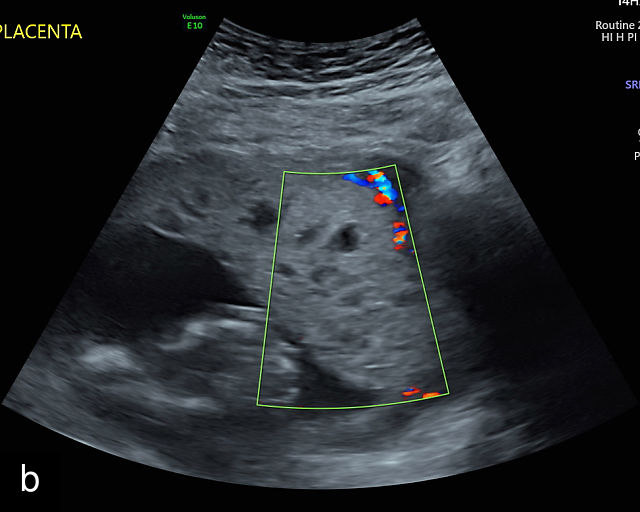

Placental lakes

Placental lakes are hypoechoic regions within the placenta and are the most common finding on ultrasound of the placenta (Figure 3; Video 1).2,9,13,16 They are surrounded by placental tissue of normal echogenicity.16 Some reports specify that hypoechoic areas should be at least 2 cm in size to qualify as lakes.13,17 On grayscale ultrasound, swirling of blood can be observed in lakes (Video 1). Low-velocity flow can be demonstrated using sensitive Doppler techniques. Lakes tend to be located in the center of placental cotyledons or under the chorionic plate (Figure 3).16 Other common locations are at the placental edge and between lobes in a bilobed placenta where they may be very large. Lakes tend to fluctuate in size over time. Several studies have found that placental lakes are not associated with an increase in adverse pregnancy outcome, regardless of size and number.13,18,19 However, one study found an increased risk of small-for-gestational age fetuses with larger placental lakes.20 Lakes must be differentiated from lacunae, which contain high-velocity blood flow and are associated with placenta accreta spectrum.16

3

(a–f) Placental lakes. Multiple hypoechoic spaces present in placenta (p), surrounded by placental tissue of normal echogenicity. Arrows in (e) and (f) indicate lakes.